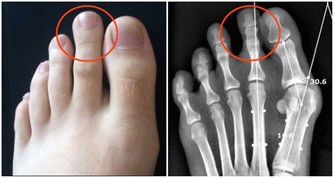

如果你的腳趾頭又瘦又短,腳部整體輪廓也是細又長,那你的身體好像不是很好喔!

因為小腳趾是足少腎經的源頭,所以小腳趾較粗較厚實的多是腎氣足的,而相反就是腎氣虧的。